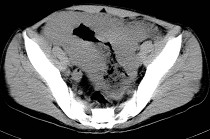

- 单项选择题男,23岁, 下腹部肿块伴持续性钝痛1月余,影像所见如图, 最可能的诊断为 ( )

A、小肠癌

B、小肠淋巴瘤

C、小肠转移瘤

D、小肠结核

E、小肠间质瘤